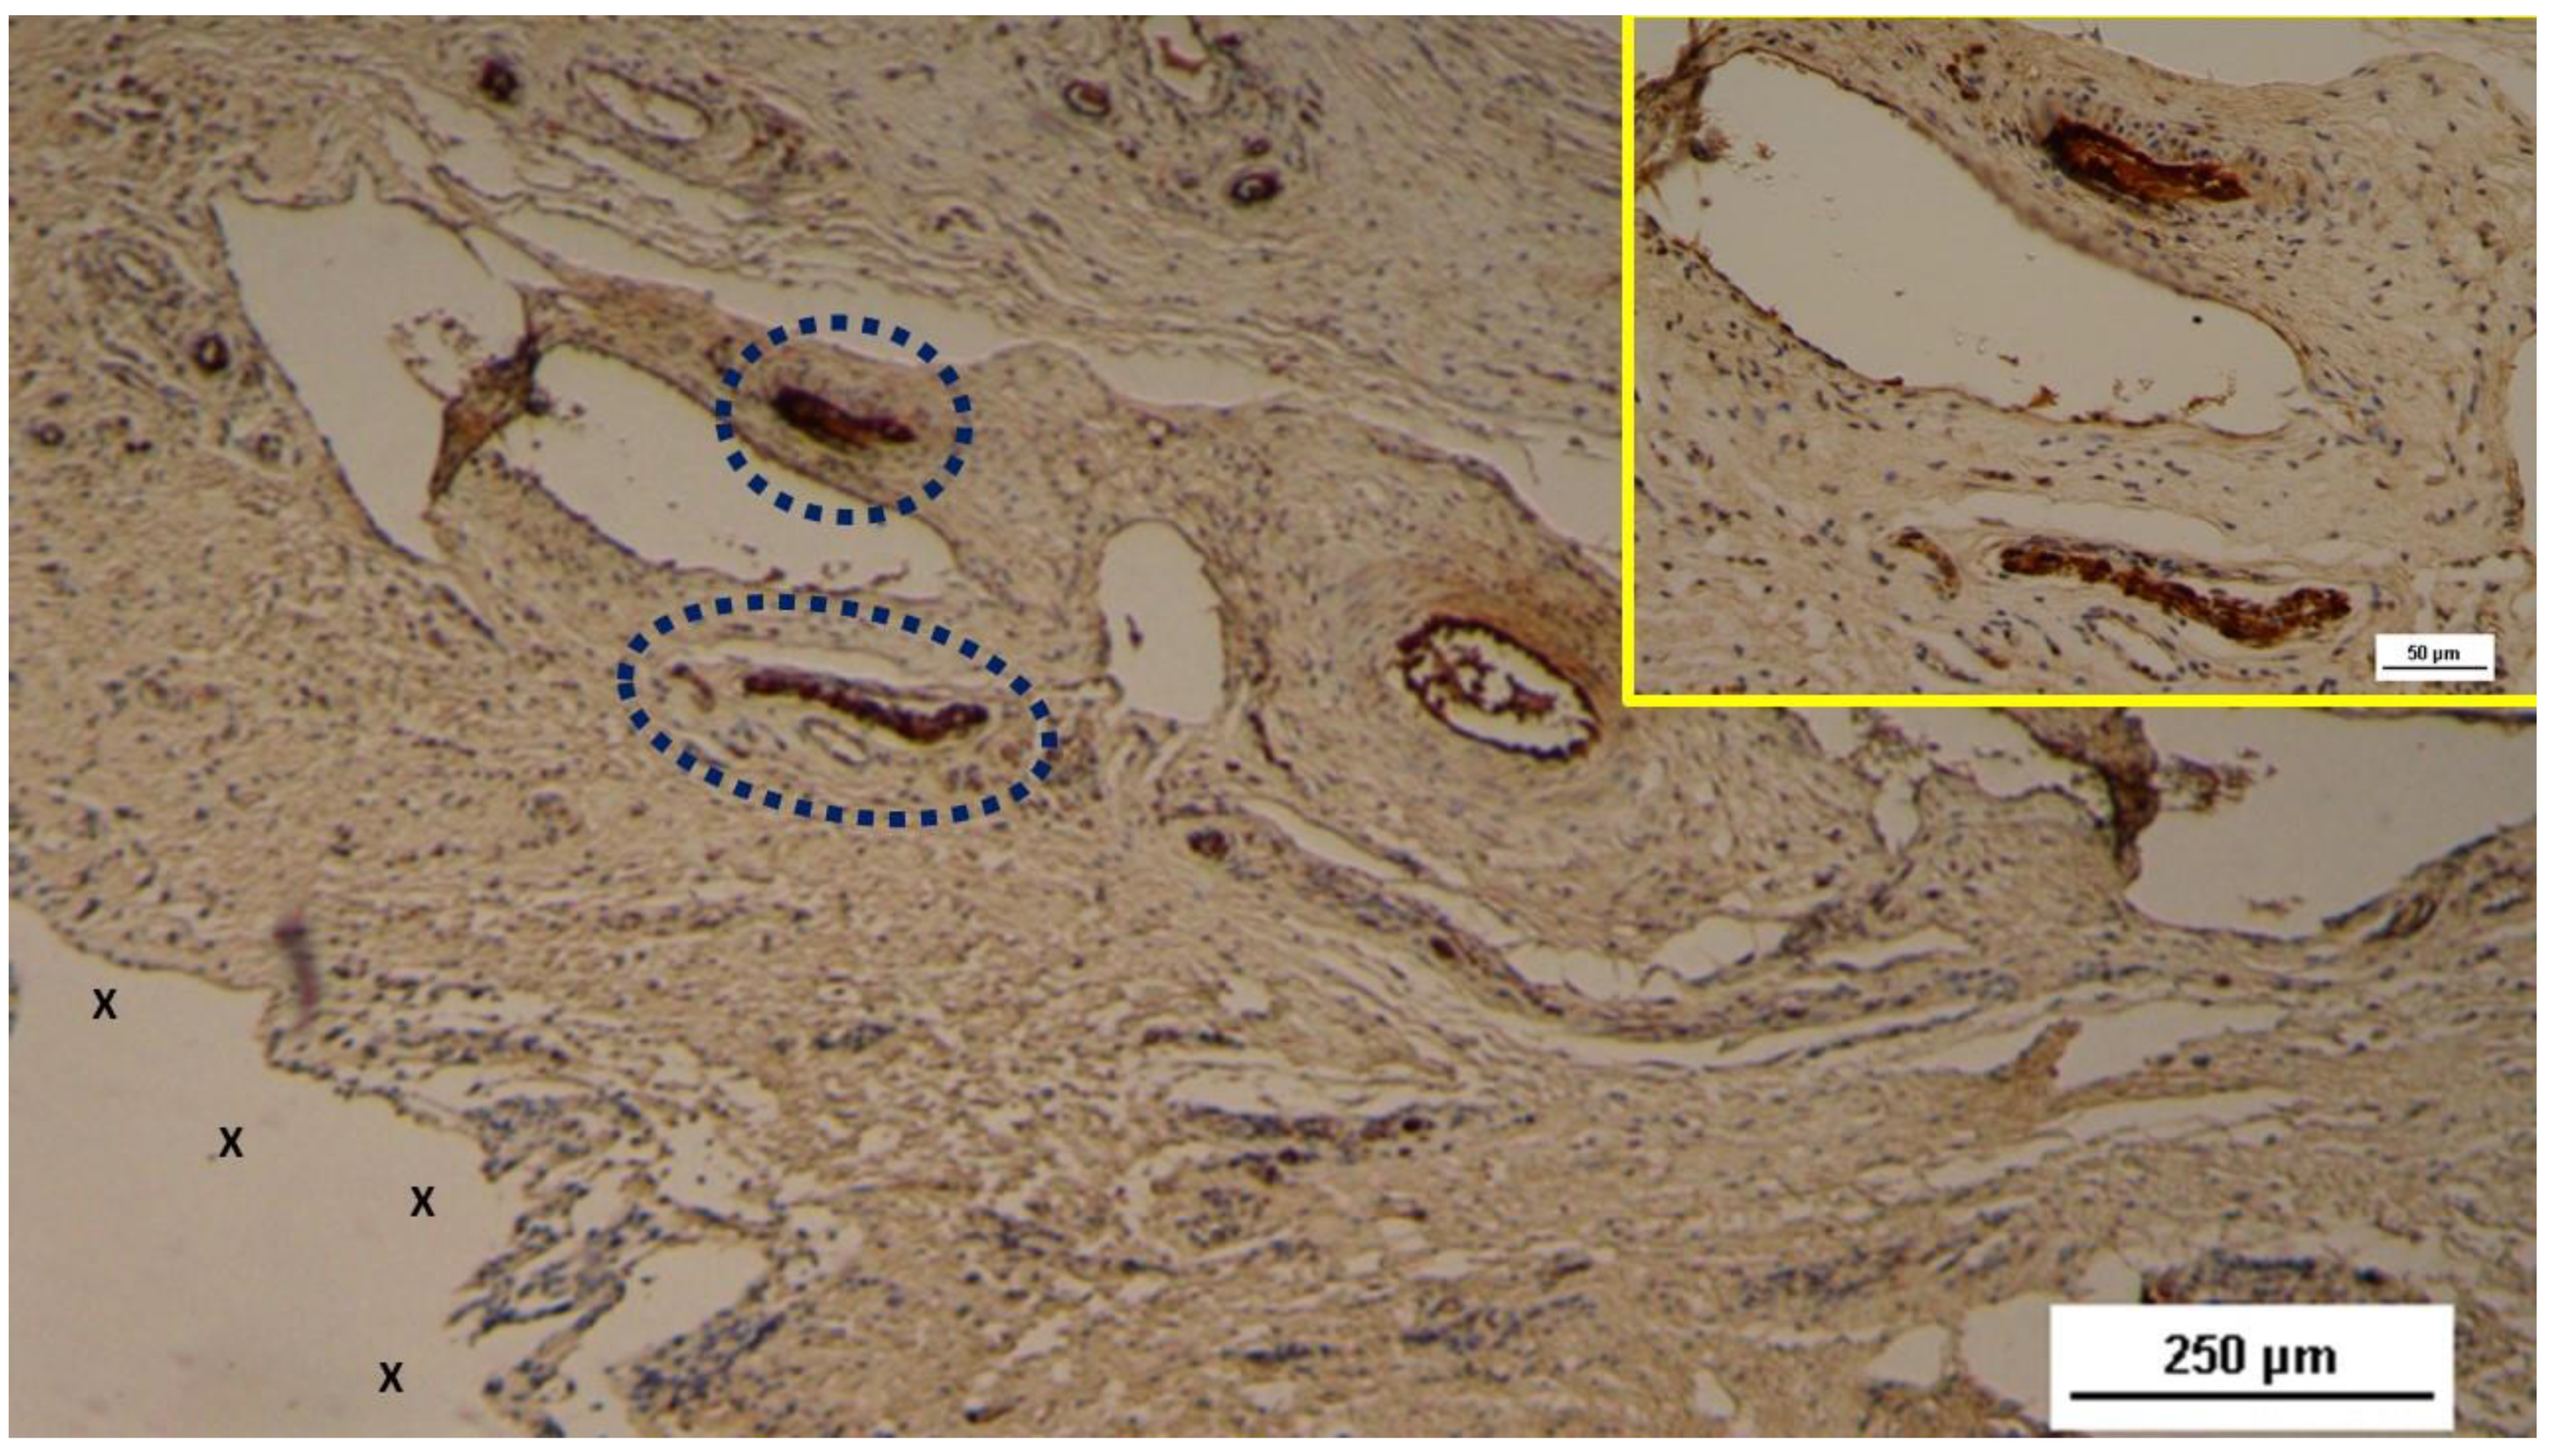

Figure 6. - Biopsy specimen excised 4 weeks post-op: Two nervous structures (blue circles) in the early stage of development, stained brown, are located near the 3D scaffold of the S&S device (X). In the upper right corner, a highly magnified image of the two neural structures (stained brown) from the main figure is displayed. NSE 50X (main image) and 200X (inset).